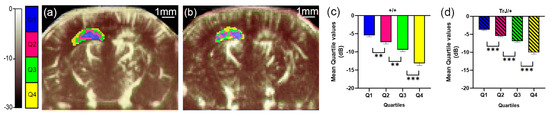

3.1. µDoppler Images Quantification

- Anzibar Fialho, M.; Vázquez Alberdi, L.; Martínez, M.; Calero, M.; Baranger, J.; Tanter, M.; Damián, J.P.; Negreira, C.; Rubido, N.; Kun, A.; et al. Intensity Distribution Segmentation in Ultrafast Doppler and Correlative Scanning Laser Confocal Microscopy for Assessing Vascular Changes Associated with Ageing in Murine Hippocampi. Sci. Rep. 2022, 12, 6784. [Google Scholar] [CrossRef]